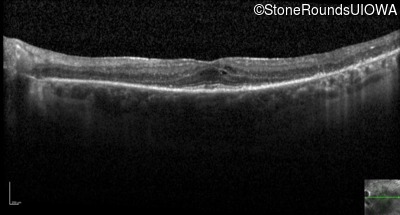

Optical Coherence Tomography - Right - 20/40 -2

Exemplar / OCT Stack

OCT Stack